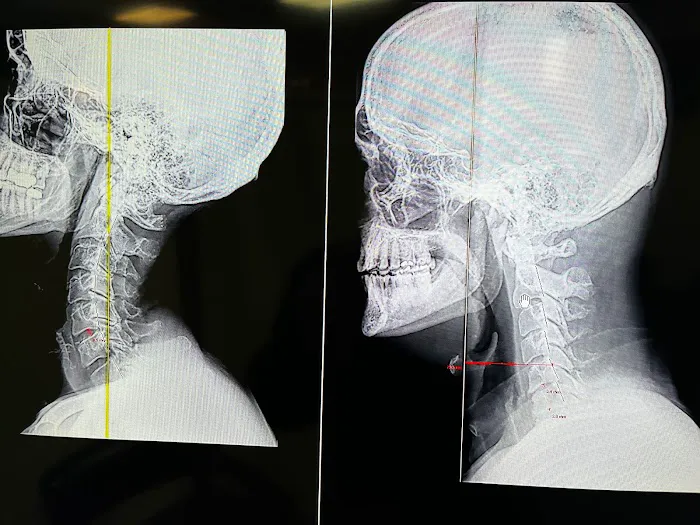

Apr 02, 2025 · Z WhiteI came to see Dr Reuben Montemangi at the suggestion of my son who knows I have suffered many issues not only with my neck and back, but headaches, sleep issues, digestive issues, and have recently had issues with my kidneys and liver. After taking a few X-rays of my neck and back, Dr Reuben actually educated me about how past physical trauma to my neck and back caused misalignment and showed me specifically where he was going to treat me with adjustments.I learned how trauma can manifest itself over many years and increase misalignment which interrupts the connections between your spine and your organs therefore causing many issues throughout your body.After my initial adjustment, my neck and lower back were feeling pretty good, and after the second visit I am feeling even better! Dr. Rubin set up a plan for me to have two adjustments a week for six weeks and will then take another set of x-rays and not only should I be feeling great, but we should be able to see the improvement of alignment in the X-rays . I will update here after I finish the the remaining treatments!